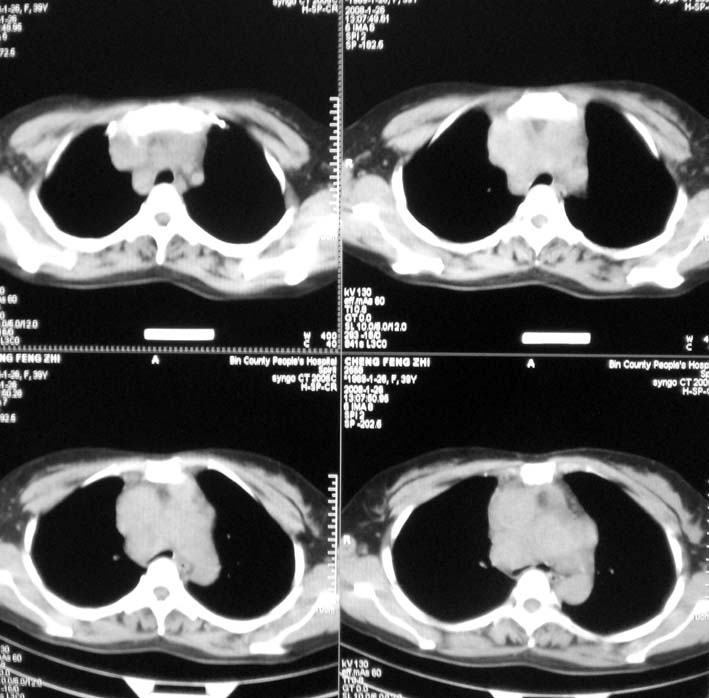

以下是引用guoke在2008-1-27 14:15:00的发言:[br]纵隔增宽,纵隔内血管境界不清,心包积液,考虑纵隔淋巴瘤.[br]

以下是引用随光逐影在2008-1-27 15:52:00的发言:[br]1)考虑为:淋巴瘤。建议:行进一步检查。2)心包积液。